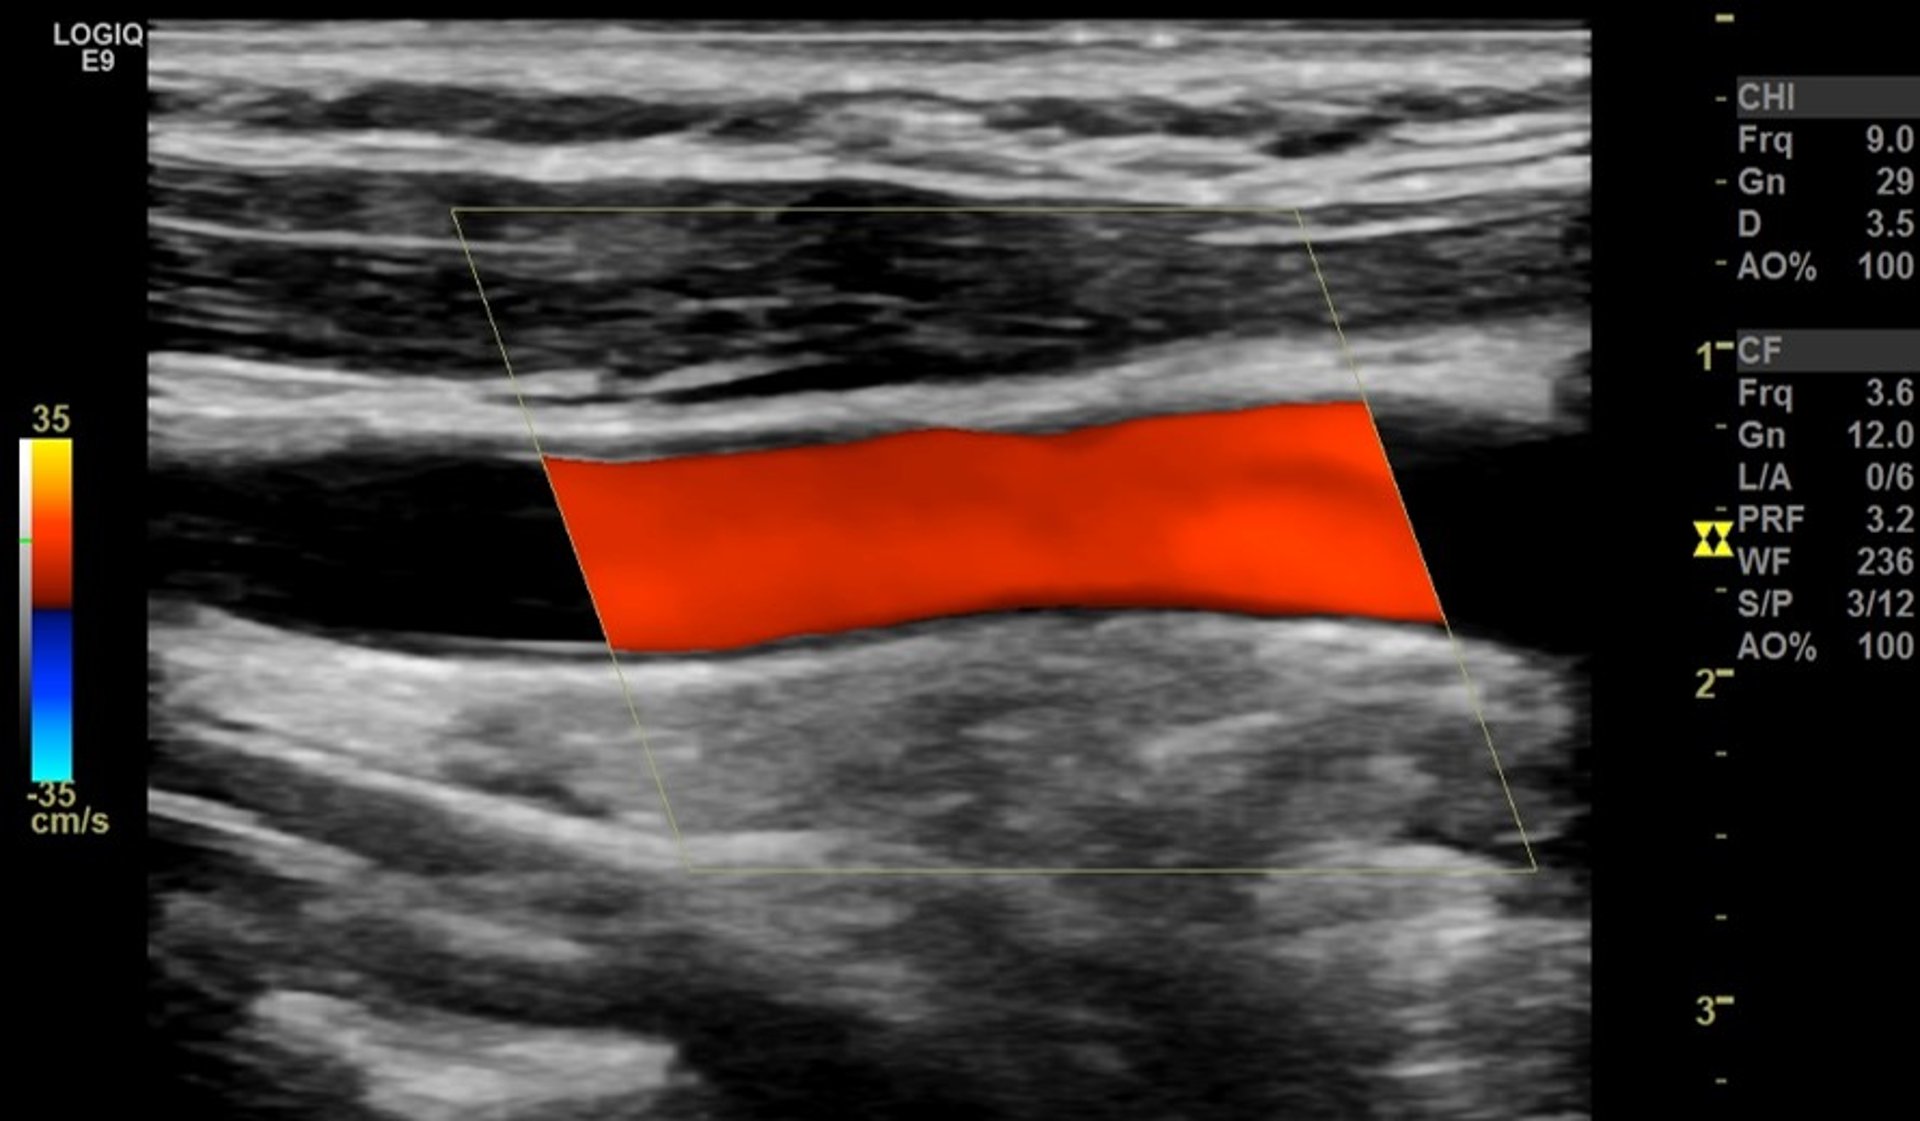

Ultrasound Doppler Warna pada Arteri Karotis

Garis merah mewakili aliran darah normal yang tidak terhalang melalui arteri besar di leher (arteri karotis komunis), dilihat dari samping.

Gambar disediakan oleh Mustafa Mafraji MD